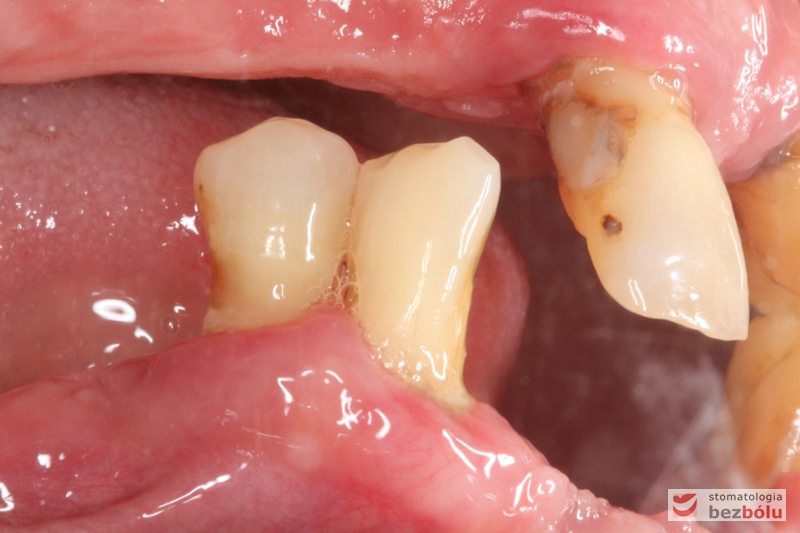

Stan wyjściowy - bez protez, liczne braki zębowe i po 2 nierokujące zęby w szczęce i żuchwie

Stan wyjściowy – bez protez, liczne braki zębowe i po 2 nierokujące zęby w szczęce i żuchwie